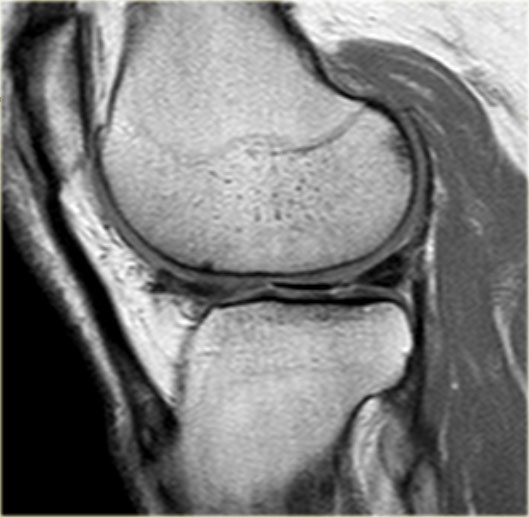

Dấu hiệu sụn chêm rỗng

Khi có rách xuyên tâm hoàn toàn, hai mảnh sụn chêm có thể bị tách rời hoàn toàn.

Điều này có thể dẫn đến hình ảnh khoang sụn chêm rỗng hay còn gọi là dấu hiệu sụn chêm rỗng (mũi tên).

TRÁI: Hình ảnh sụn chêm vắng mặt hoặc rỗng trên mặt phẳng đứng dọc. PHẢI: Hình ảnh mặt cắt ngang cho thấy rách xuyên tâm hoàn toàn dẫn đến khuyết hổng sụn chêm.

Nếu khảo sát một đường rách xuyên tâm hoàn toàn trực tiếp dọc theo chiều dài của đường rách, bạn sẽ thấy hình ảnh sụn chêm vắng mặt hoặc rỗng.

Các đường rách xuyên tâm hoàn toàn này mở ra và tạo ấn tượng rằng có một phần sụn chêm bị thiếu.

Tuy nhiên, bạn sẽ không tìm thấy mảnh sụn chêm bị di lệch.

Đây đơn thuần chỉ là sự tách rời của các phần sụn chêm.

Hình bên trái minh họa một đường rách xuyên tâm hoàn toàn, có thể dẫn đến dấu hiệu sụn chêm rỗng.